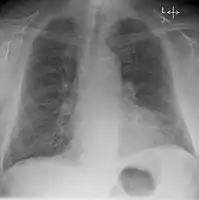

Chest X-ray

Chest radiograph of a lung with distinct Kerley B lines, as well as an enlarged heart (as shown by an increased cardiothoracic ratio, cephalization of pulmonary veins, and minor pleural effusion as seen for example in the right horizontal fissure. Yet, there is no obvious lung edema. Overall, this indicates intermediate severity (stage II) heart failure.

Chest X-rays are frequently used to aid in the diagnosis of CHF. In a person who is compensated, this may show cardiomegaly (visible enlargement of the heart), quantified as the cardiothoracic ratio (proportion of the heart size to the chest). In left ventricular failure, there may be evidence of vascular redistribution ("upper lobe blood diversion" or "cephalization"), Kerley lines, cuffing of the areas around the bronchi, and interstitial edema. Ultrasound of the lung may also be able to detect Kerley lines.[39]